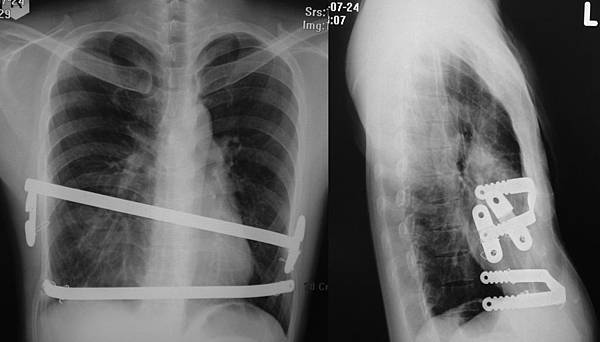

沒想到還有這個用途....矯正板意外時額外的保護.

一位年輕病友, 三年前手術, 裝了二條矯正板, 預計今年要來移除的, 卻在四個月前發生嚴重車禍, 當時可能車速很快, 在嚴重撞擊後, 有胸部及腹部鈍傷, 他的左胸肋骨斷了五條, 有兩側大量血胸, 胃破裂, 脾臟破裂, 在南部醫院做了兩側胸管引流, 胃修補手術, 及脾臟切除手除, 當時急救的醫師說, 幸而有矯正板保護了心臟, 不然這麼大的撞擊, 可能情況會更嚴重. 在近千例病友中, 這已是第二例了